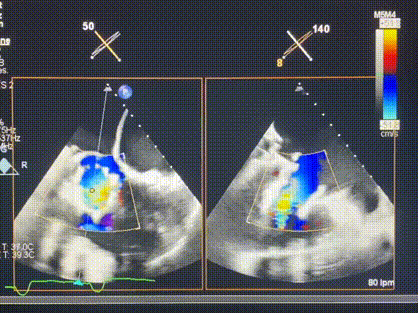

術后超聲顯示僅殘余微量瓣周漏

LuX-Valve Plus經(jīng)血管三尖瓣置換系統(tǒng)此次“出海”圓滿完成,術后Rodrigo Estévez-Loureiro教授對LuX-Valve Plus經(jīng)血管三尖瓣置換系統(tǒng)的器械性能和治療效果大為稱贊,認為LuX-Valve Plus的手術體驗非常好。術后即刻超聲顯示三尖瓣反流幾乎完全消失,血流動力學改善顯著,患者恢復快。在面對復雜解剖結構、超聲影像質(zhì)量不佳、有起搏導線干擾時,Lux-Valve Plus也體現(xiàn)了極強的適應性。Thomas Modine教授和Anson Cheung教授也肯定了LuX-Valve Plus術中操作的便捷性,認為LuX-Valve Plus容錯率高,對術中影像的依賴較小,后期希望可以更多的應用LuX-Valve Plus三尖瓣置換系統(tǒng)于臨床實踐,讓更多的三尖瓣重度反流患者盡早獲益,改善預后。